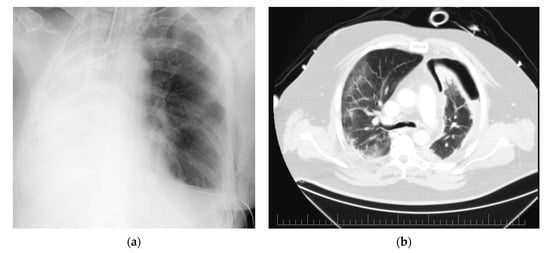

4.1. Case 1

4.2. Case 2